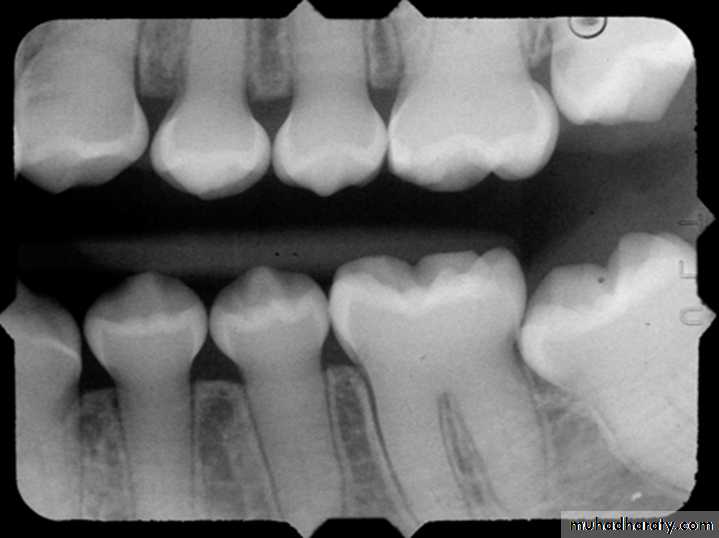

Difference between amelogenesis imperfecta and Dentinogenesis imperfecta

Amelogenesis imperfect

Normal root

Dentinogenesis imperfect

Abnormal root